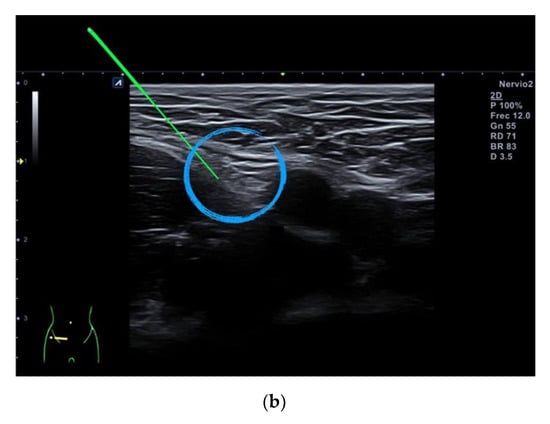

2.4. Percutaneous Electrical Nerve Stimulation